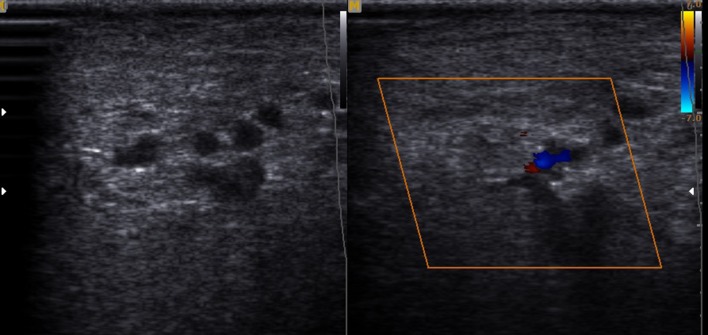

Herein, we report the case of a 16-year-old female who presented to the orthopaedics clinic with the complaint of a painless soft tissue swelling involving the right ankle and foot. She first noted the swelling at about 8 years of age. Initially, it was small, but later, the lesion gradually painlessly progressed to the present size. It completely surrounded the ankle and the heel region. The involved region experienced overgrowth compared to that on the opposite side. The skin over the swelling was normal with no evidence of any discolouration. On palpation, the temperature of the lesion was not raised. The lesion was soft to touch, but it was not possible to distinguish the margins from the adjacent normal area, suggesting an ill-defined lesion. In consistency with the examination findings, the provisional diagnosis of a vascular malformation was considered. The patient was subjected to ultrasonography. It showed an increase in the thickness of the soft tissue, which appeared hyperechoic, comparable to the adjacent normal fat density with multiple interspersed hypoechoic areas within it (Fig. 1). On colour Doppler evaluation, these hypoechoic areas showed slow flow, which it was better to appreciate on power Doppler (Fig. 2). These findings were consistent with the diagnosis of a vascular malformation. However, the duration of the progression of the supposed vascular malformation and the absence of phleboliths on the ultrasound and the subsequent X-ray raised suspicion regarding the diagnosis of a vascular malformation. A second differential of a neurofibroma was considered. Subsequently, a biopsy was conducted. It showed elongated spindle cells with poorly defined, pale eosinophilic cytoplasm and tapering, wavy, or buckled nuclei admixed with a few small nerve fibres (Fig. 3). Immunohistochemistry showed positivity for S-100 (Fig. 4). These findings were consistent with the diagnosis of diffuse neurofibroma.

Fig. 2.

On colour Doppler evaluation, these hypoechoic areas showed vascular flow. However, no phleboliths were noted within the lesion

On ultrasonography, the superficial subcutaneous lesions appear to be hyperechoic masses fenestrated by hypoechoic foci that represent the blood vessels [1, 4]. Similar findings were noted in the present case. However, few reported cases show deeper involvement of the structures, presenting as hypoechoic masses infiltrating the adjacent structures [4]. Ultrasound has been agreed upon as the initial modality of investigation due to its easy availability, lack of radiation exposure, and cost-effectiveness [1, 3, 4]. However, more deeply infiltrating lesions may require an MRI to delineate their exact extents. On MRI, most of these lesions are depicted as isointense or mildly hyperintense compared to muscle on T1-weighted images and mildly or markedly hyperintense compared to muscle on T2-weighted images. Such findings have been consistently described in various case reports [4, 8].